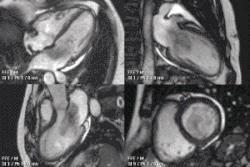

Bardzo często śluzak serca wykrywany jest po zatorowym udarze mózgu, lub po zatorze obwodowym. W diagnostyce bardzo ważna jest echokardiografia uzupełniana badaniami tomografią komputerową lub rezonansem magnetycznym[2].

Śluzak serca – najczęstszy łagodny nowotwór serca, występujący trzykrotnie częściej u kobiet, rozwijający się z wsierdzia ściennego[2]. Pojawia się niemal wyłącznie w przedsionkach, najczęściej w lewym – w 86%[3], może pojawić się w każdym wieku, ale szczyt występuje między czterdziestym, a pięćdziesiątym rokiem życia[2]. Jest rozrostem polipowym. W typowej postaci ma on kształt kulistego, miękkiego zgrubienia na cienkiej nóżce (szypule), zawierającej wiązkę naczyń odżywiających, która umożliwia przemieszczanie się guza. Przemieszczanie się śluzaka przez zastawkę mitralną, lub trójdzielną może powodować ich dysfunkcję z objawami niedomykalności zastawki mitralnej, lub niedomykalność zastawki trójdzielnej i/lub zwężenia (stenozy)[2]. Cały nowotwór jest pokryty śródbłonkiem. W około 10% przypadków śluzak serca występuje rodzinnie jako składowa zespołu Carneya. U pacjentów często obserwuje się tzw. Triadę objawów: